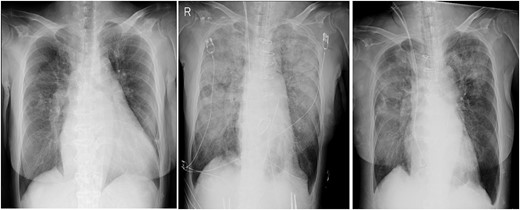

In the intensive care unit, a high positive end-expiratory pressure (PEEP) was required at 12–16 cmH2O, with a peak inspiratory pressure of 30 cmH2O and FIO2 of 1.0. Nonetheless, arterial blood gas showed a pH of 6.99, pO2 of 77.7 mmHg and pCO2 of 107 mmHg. Meanwhile, cardiac function was comparatively maintained, with a cardiac index of ~2.4 l/min/m2. Chest radiography (CXR) showed bilateral consolidation as well as remarkable shrinkage of the cardiac silhouette compared to the preoperative CXR (Fig. 1), suggesting an extremely low left atrial pressure. Therefore, VV-ECMO (Capiox; Terumo Inc, Tokyo, Japan) was immediately initiated after placing a 21 Fr drainage cannula in the right atrium through the right femoral vein and a 15 Fr return cannula through the left femoral vein, guided by ultrasonography. Nafamostat mesilate was used for anticoagulation with a target-activated clotting time (ACT) of 180 s. Within 12 h post-operatively, the patient achieved hemodynamic stability with the administration of catecholamine and fluid replacement, including blood transfusion. The amount of yellowish sputum in the tracheal tube decreased significantly, reaching nearly 4000 ml in total. To compensate for the fluid and protein loss, 14 units (1680 ml) of FFP, 500 ml (100 g) of 20% albumin solution and 3000 ml of crystalloid solutions were intravenously administered over 12 h. No significant bleeding or fluid loss from the surgical site was observed.

Chest radiographs obtained pre-operation (left), post-operation (middle) and 2 days post-operatively (right).

On post-operative day (POD) 2, VV-ECMO was discontinued after noting significant improvement with mechanical ventilation with PEEP at 12 cmH2O and FIO2 at 0.45. The ECMO duration was 39 h. Mechanical ventilatory support was terminated on POD 14. The patient required rehabilitation because of post-intensive care syndrome and was discharged on POD 70.